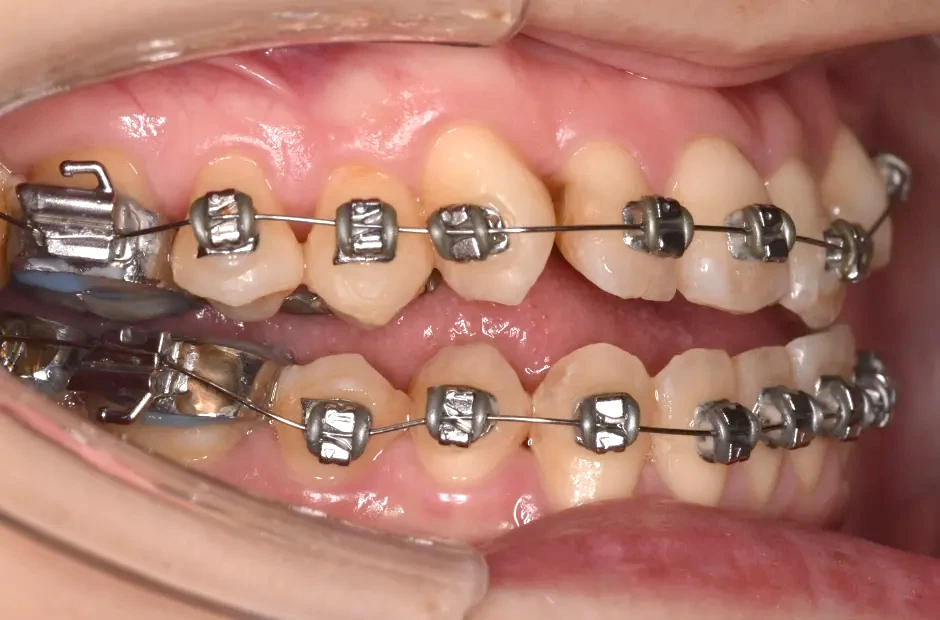

叢生

| 診断名・主訴 | 叢生 |

|---|---|

| 年齢・性別 | 43歳・女性 |

| 治療期間・回数 | 2年7か月 27回 |

| 治療に用いた主な装置 | 舌側矯正 |

| 抜歯部位 | 両顎4,4 |

| 治療費 | 100万円(税抜) |

| リスク・副作用 | 装置による違和感・疼痛・歯肉退縮・歯根吸収・虫歯のリスクなど |

治療中